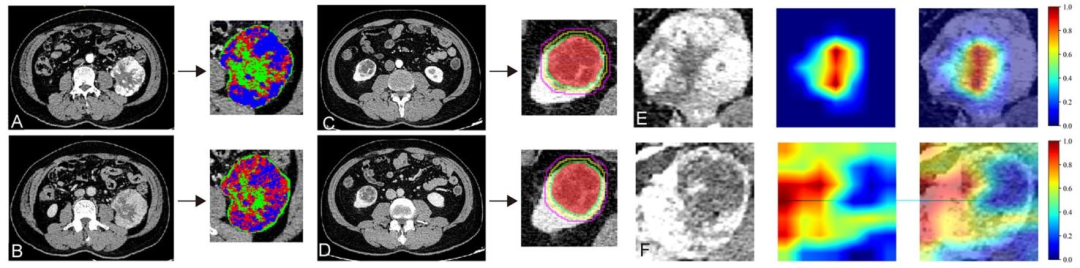

图 7:生境成像、瘤周分割和DL模型可解释性的可视化